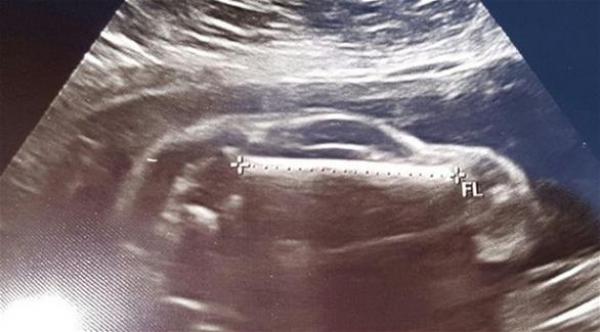

نشر رجل أمريكي صورة الأمواج الصوتية التي أجريت لزوجته الحامل، ويظهر فيها الجنين على شكل سيارة رياضية.

وشارك الأب هذه الصورة الغريبة عبر موقع التواصل الاجتماعي "ريديت"، بعد أن لاحظ أن الجنين الذي ينتظره يظهر في الصورة على شكل سيارة، وأثارت هذه الصورة موجة من التعليقات الطريفة على الإنترنت، بحسب ما ذكرت صحيفة ميرور البريطانية.